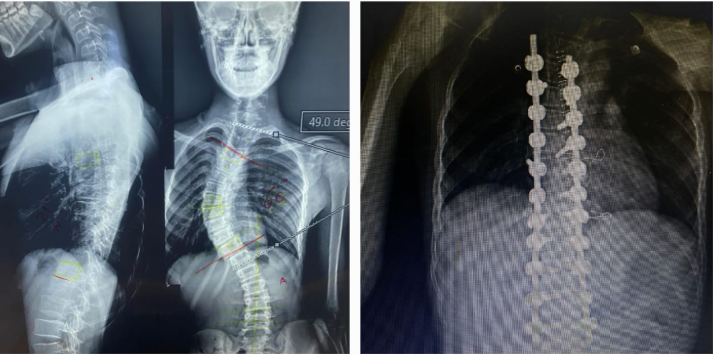

A medical team at Beni Suef University Hospitals succeeded in Scoliosis Correction Surgery for a patient.

2 Oct 2025